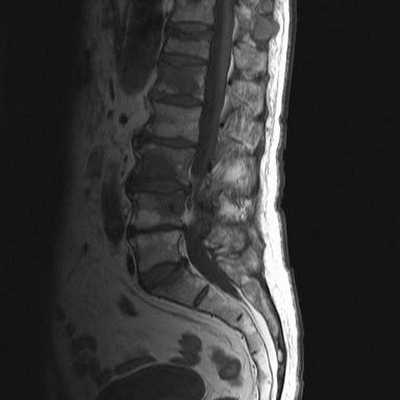

Среди экстрадуральных опухолей на первом месте стоит метастатическое поражение. Стандартный протокол МРТ исследования позвоночника при подозрении на метастатическое поражение состоит из Т1-зависимых сагиттальных МРТ и Т2-зависимых МРТ с подавлением сигнала от жира. Литические метастазы замещая костный мозг выглядят гипоинтенсивными на Т1-зависимых МРТ позвоночника. На Т2-зависимых МРТ позвоночника они могут быть гипоинтенсивными, изоинтенсивными, если они склеротические, либо яркими, если они литические, особенно при подавлении сигнала от жира. Метастаз может диффузно поражать костный мозг позвонка или быть очаговым. На самой ранней стадии диффузного поражения при МРТ позвоночника заметно исчезновение сигнала от вертебробазилярной вены, процесс захватывает ножки дуг и задние структуры позвонка. Распространение на мягкие ткани вдоль позвоночника лучше видно на Т1-зависимых корональных МРТ, а сдавление спинного мозга на сагиттальных МРТ позвоночника. На последнем этапе желательны контрастированные Т1-зависимые МРТ в сагиттальной и поперечной плоскостях. Чуствительность МРТ позвоночника превышает 90%, что заметно превосходит радионуклидную диагностику. В плане отличия метастазов и доброкачественных заболеваний МРТ позвоночника не абсолютно надежна. Дифференциальная диагностика с гематологической патологией - плазмоцитомой, лимфомой и лейкозами практически невозможна и требует аспирационной биопсии. Реакцией костного мозга на МРТ позвоночника, напоминающей метастатическое поражение, сопровождаются доброкачественные переломы. Однако МРТ сигнал выраженно неоднородный, задние структуры и костный мозг в заднем отделе тела позвонка остаются интактными. Более надёжным в плане дифференциальной диагностики является использование диффузионное-взвешенных МРТ позвоночника. При доброкачественном переломе через 1 - 3 месяца сигнал возвращается к норме.

Метастазы в позвонки. Т2-зависимая МРТ.